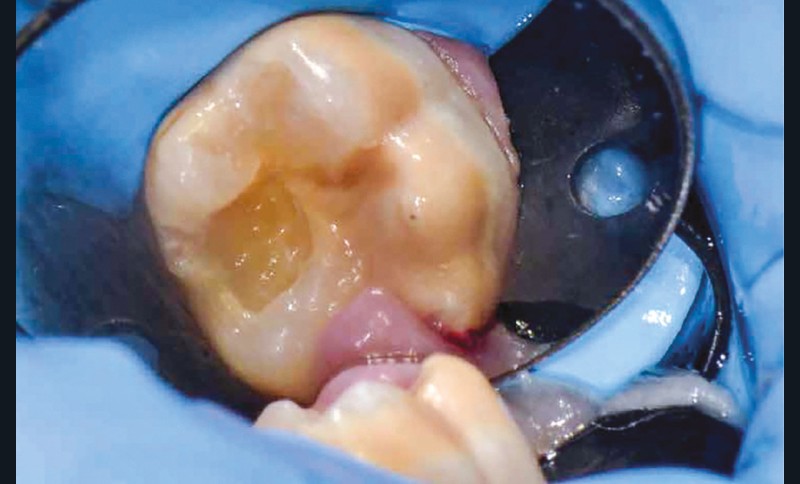

Lisa est une jeune patiente de 10 ans, atteinte d’une MIH sévère sur les premières molaires mandibulaires 36 et 46 (fig. 1 et 2). Elle présente une sensibilité exacerbée au froid en regard des zones molaires entraînant un brossage approximatif.

Afin d’optimiser les séances de soins, l’anesthésie intra-osseuse par injection électronique a été réalisée avec le Quicksleeper 5® dans les deux secteurs (fig. 3 et 4) afin de permettre la réalisation des coiffes préformées métalliques sur 36 et 46 dans la même séance (fig. 5 à 7). Il aurait été difficilement envisageable de réaliser les coiffes dans la même séance en utilisant une anesthésie tronculaire dans chaque secteur.